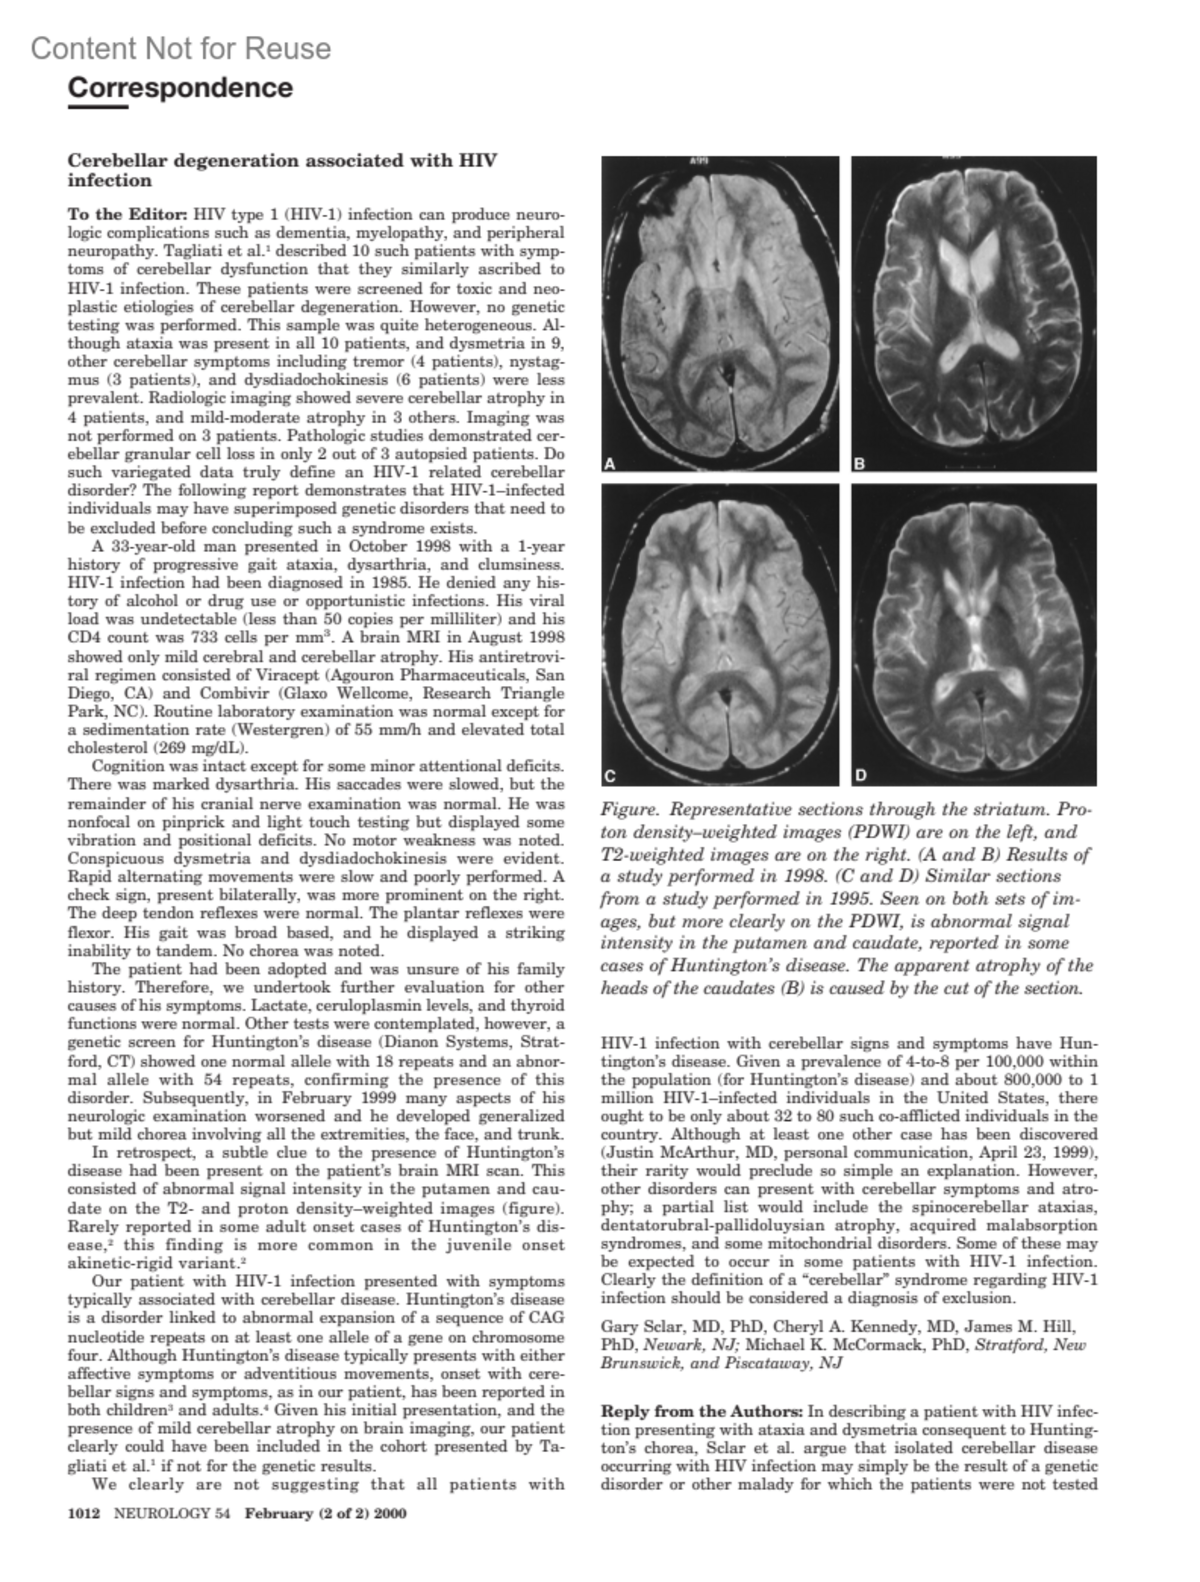

Contrast agent neurotoxicity presenting as subarachnoid hemorrhageSharp, Stephen J. MDAuthor informationChapel Hill, NCNeurology 54(4):p 1014, February 22, 2000.Copyright © 2000 American Academy of Neurology